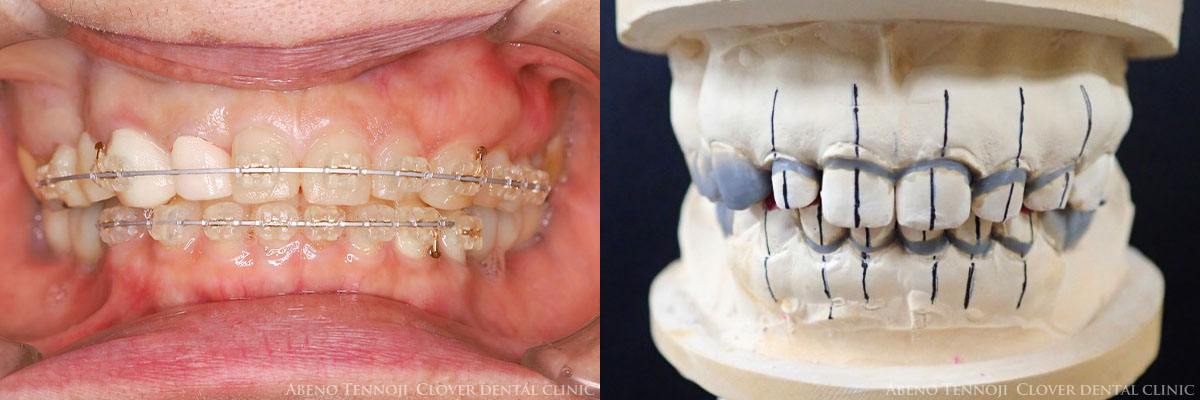

歯の裏側に装置を付けるのが裏側矯正です。

従来の裏側矯正よりも発音がしやすさや違和感の少なさが特徴の最先端の舌側矯正の装置を使用します。

歯の表面ではなく舌側にブラケットを付けるため、装置が見えない形で矯正治療を進めることができます。

裏側矯正の大きなメリットは「見た目」です。矯正装置を付けていることを気にすることなく日常生活を送ることができます。

また、裏側矯正は後ろに動かすのが得意なため、前歯を後方にスムーズに動かすことができます。